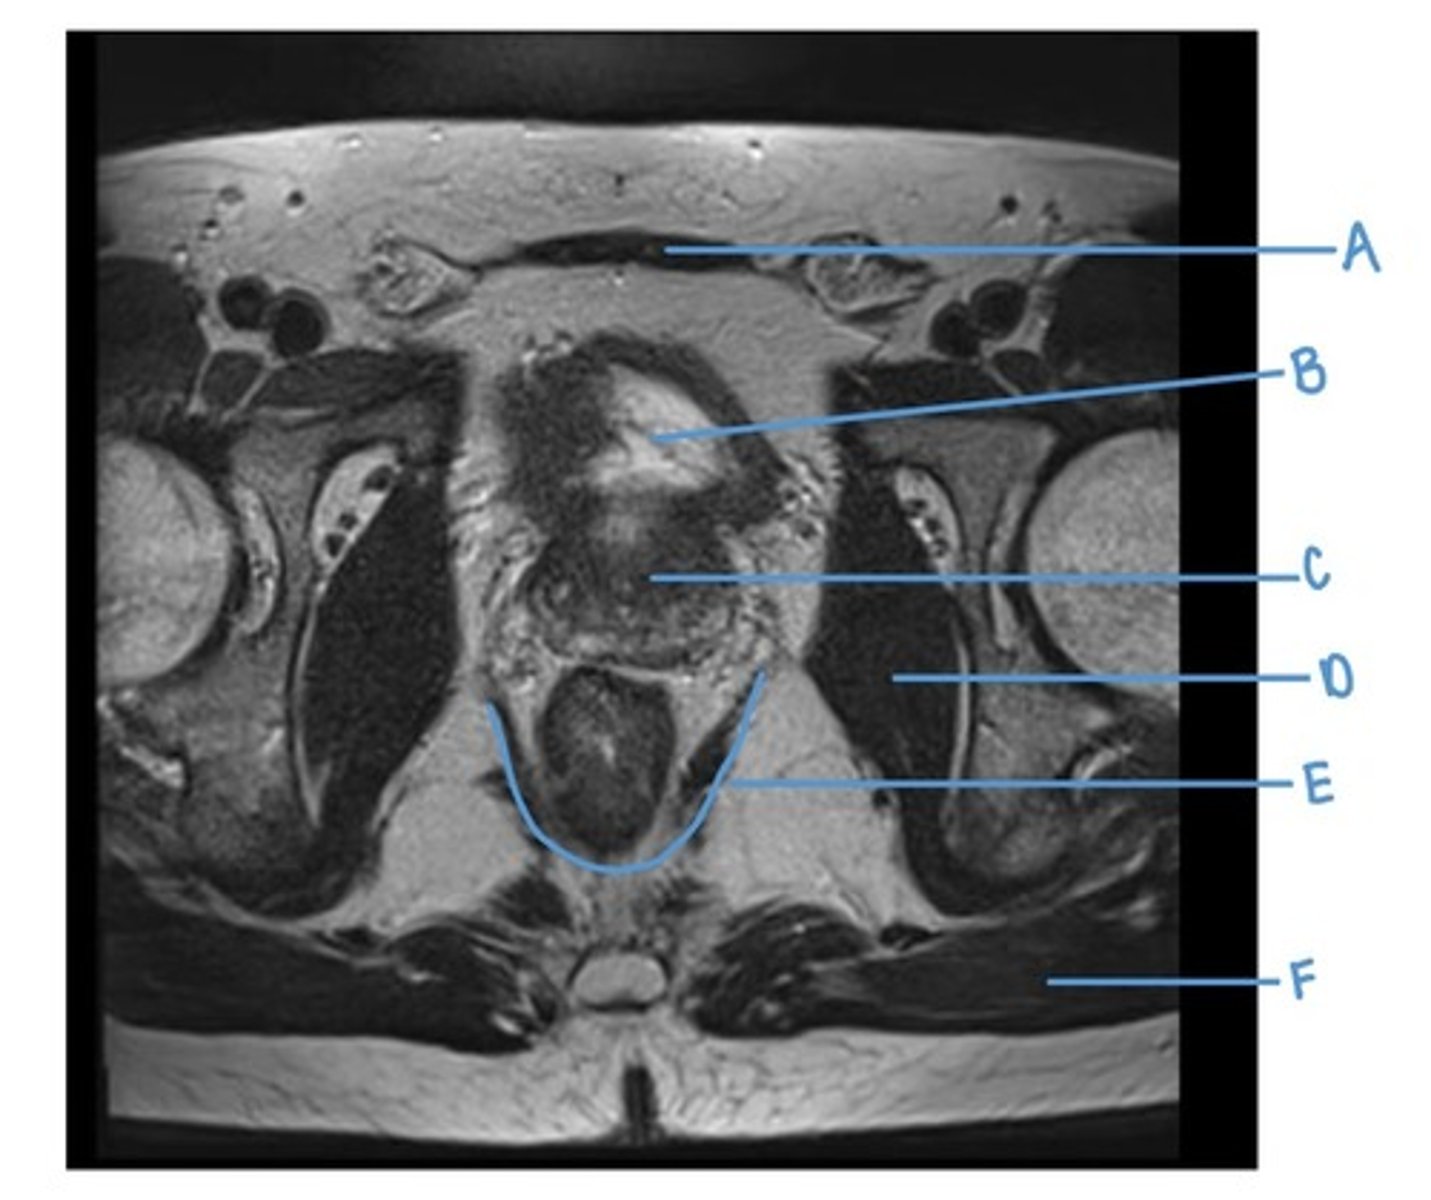

superior pubic ramus

A

rectus abdominus muscle

B

iliopsoas muscle

C

obturator internus muscle

D

rectum

E